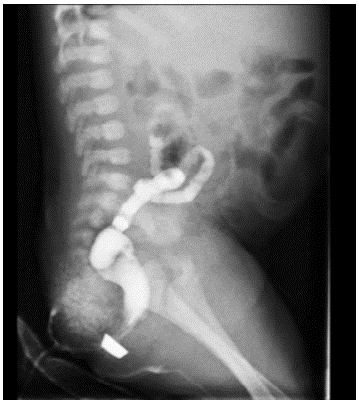

Colostomy was closed after 11 months, during which time instillations of saline solution were made through the rectum to stimulate the growth of the hypotrophic intestine. A barium enema was made before the procedure (Figure 4).

Hypoplasia of distal colon.

Figure 4: Hypoplasia of distal colon.

Source: Own elaboration based on the data obtained in the study.